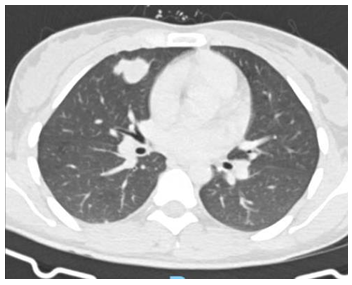

Debido a este hallazgo, con sospecha de enfermedad trofoblástica gestacional maligna se decide solicitar estudios de extensión TC tórax(Imagen 1), abdomen y pelvis(Imagen 2) en los cuales se evidencian múltiples lesiones focales en ambos campos pulmonares, destacándose por su tamaño, aquella ubicada en región anterior del campo pulmonar derecho, comprometiendo lóbulo medio y lóbulo superior, de 25mm. Sugieren valorar secundarismo. El hígado presenta múltiples lesiones focales heterogéneas, con realce con el contraste endovenoso, la mayor a nivel del segmento Vll, de 60mm, vinculables a secundarismo en primer término. Bazo de tamaño conservado, con lesión de semejantes características a las descritas en hígado, de 42mm, asimismo sugerente de secundarismo. Útero ausente en relación a los cambios descritos. Se observan aparentes engrosamientos nodulares a nivel del lecho quirúrgico, que realzan tras la administración de contraste EV y sugieren la presencia de implantes.

Imagen 1. TC tórax al diagnóstico